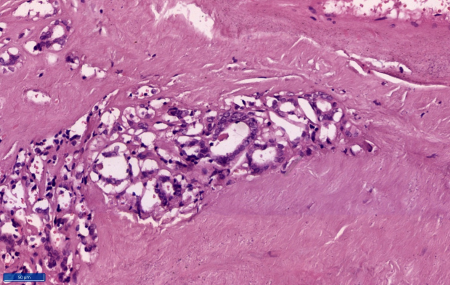

consistency. At microscopy sections showed a duct

made up of fibrous wall with extensive calcific

areas. The lumen of the duct showed a tumor

comprising of cells in predominantly papillary

pattern along with occasional follicle formations.

Individual cells lining the papillae and the

follicles showed crowding and overlapping. These

tumour cells demonstrated moderate eosinophilic

cytoplasm, mild nucleomegaly, round to oval with a

single nucleus showing nuclear clearing,

margination of the chromatin and occasional intra

nuclear grooves. Scanty mitosis were also noted.

The wall of the duct shows normal thyroid

follicles and chronic inflammation. The tumour

cells were embedded in the duct walls at places.

However, tumour cells were not extending beyond

the duct. (Figure 3-6) Hence a final diagnosis of

papillary carcinoma of thyroid-classic type (PTC),

arising in a thyroglossal duct cyst was made.

| Figure

3: Section shows cyst with tumour within

it (Haematoxylin and Eosin, x 40) |

5: Section shows tumour cells trapped

within the cyst wall. (Haematoxylin and

Eosin, x 100) |